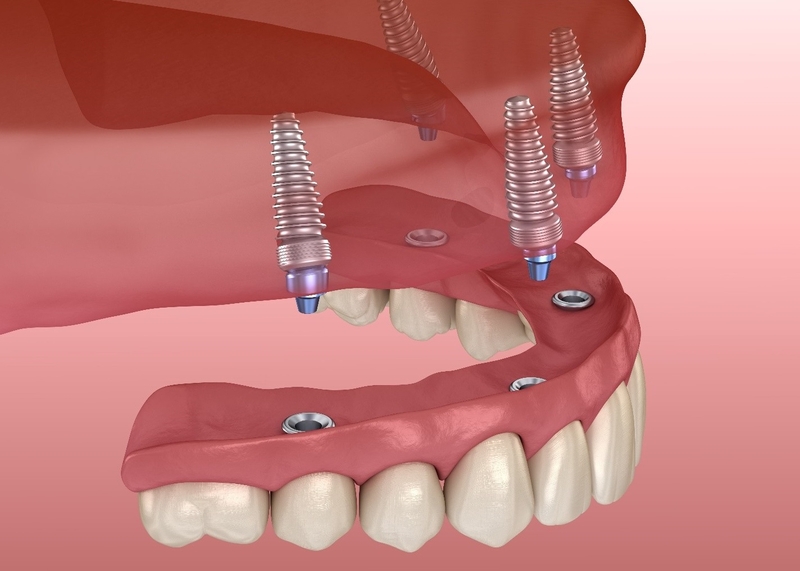

Phương pháp trồng răng implant: Với phương pháp phục hình răng số 7 bị mất này, một chân răng nhân tạo sẽ được cấy ghép vào xương hàm. Chân răng này được kết nối với abutment rối sau đó mão sứ giống như một chiếc răng thật được chụp lên trên. Ưu điểm của phương pháp này là chiếc răng được phục hình rất giống răng thật. Mão răng có tính thẩm mỹ và độ chắc chắn cao. Trụ implant thay thế chân răng nên giúp phòng tránh nguy cơ tiêu xương hàm do mất răng.